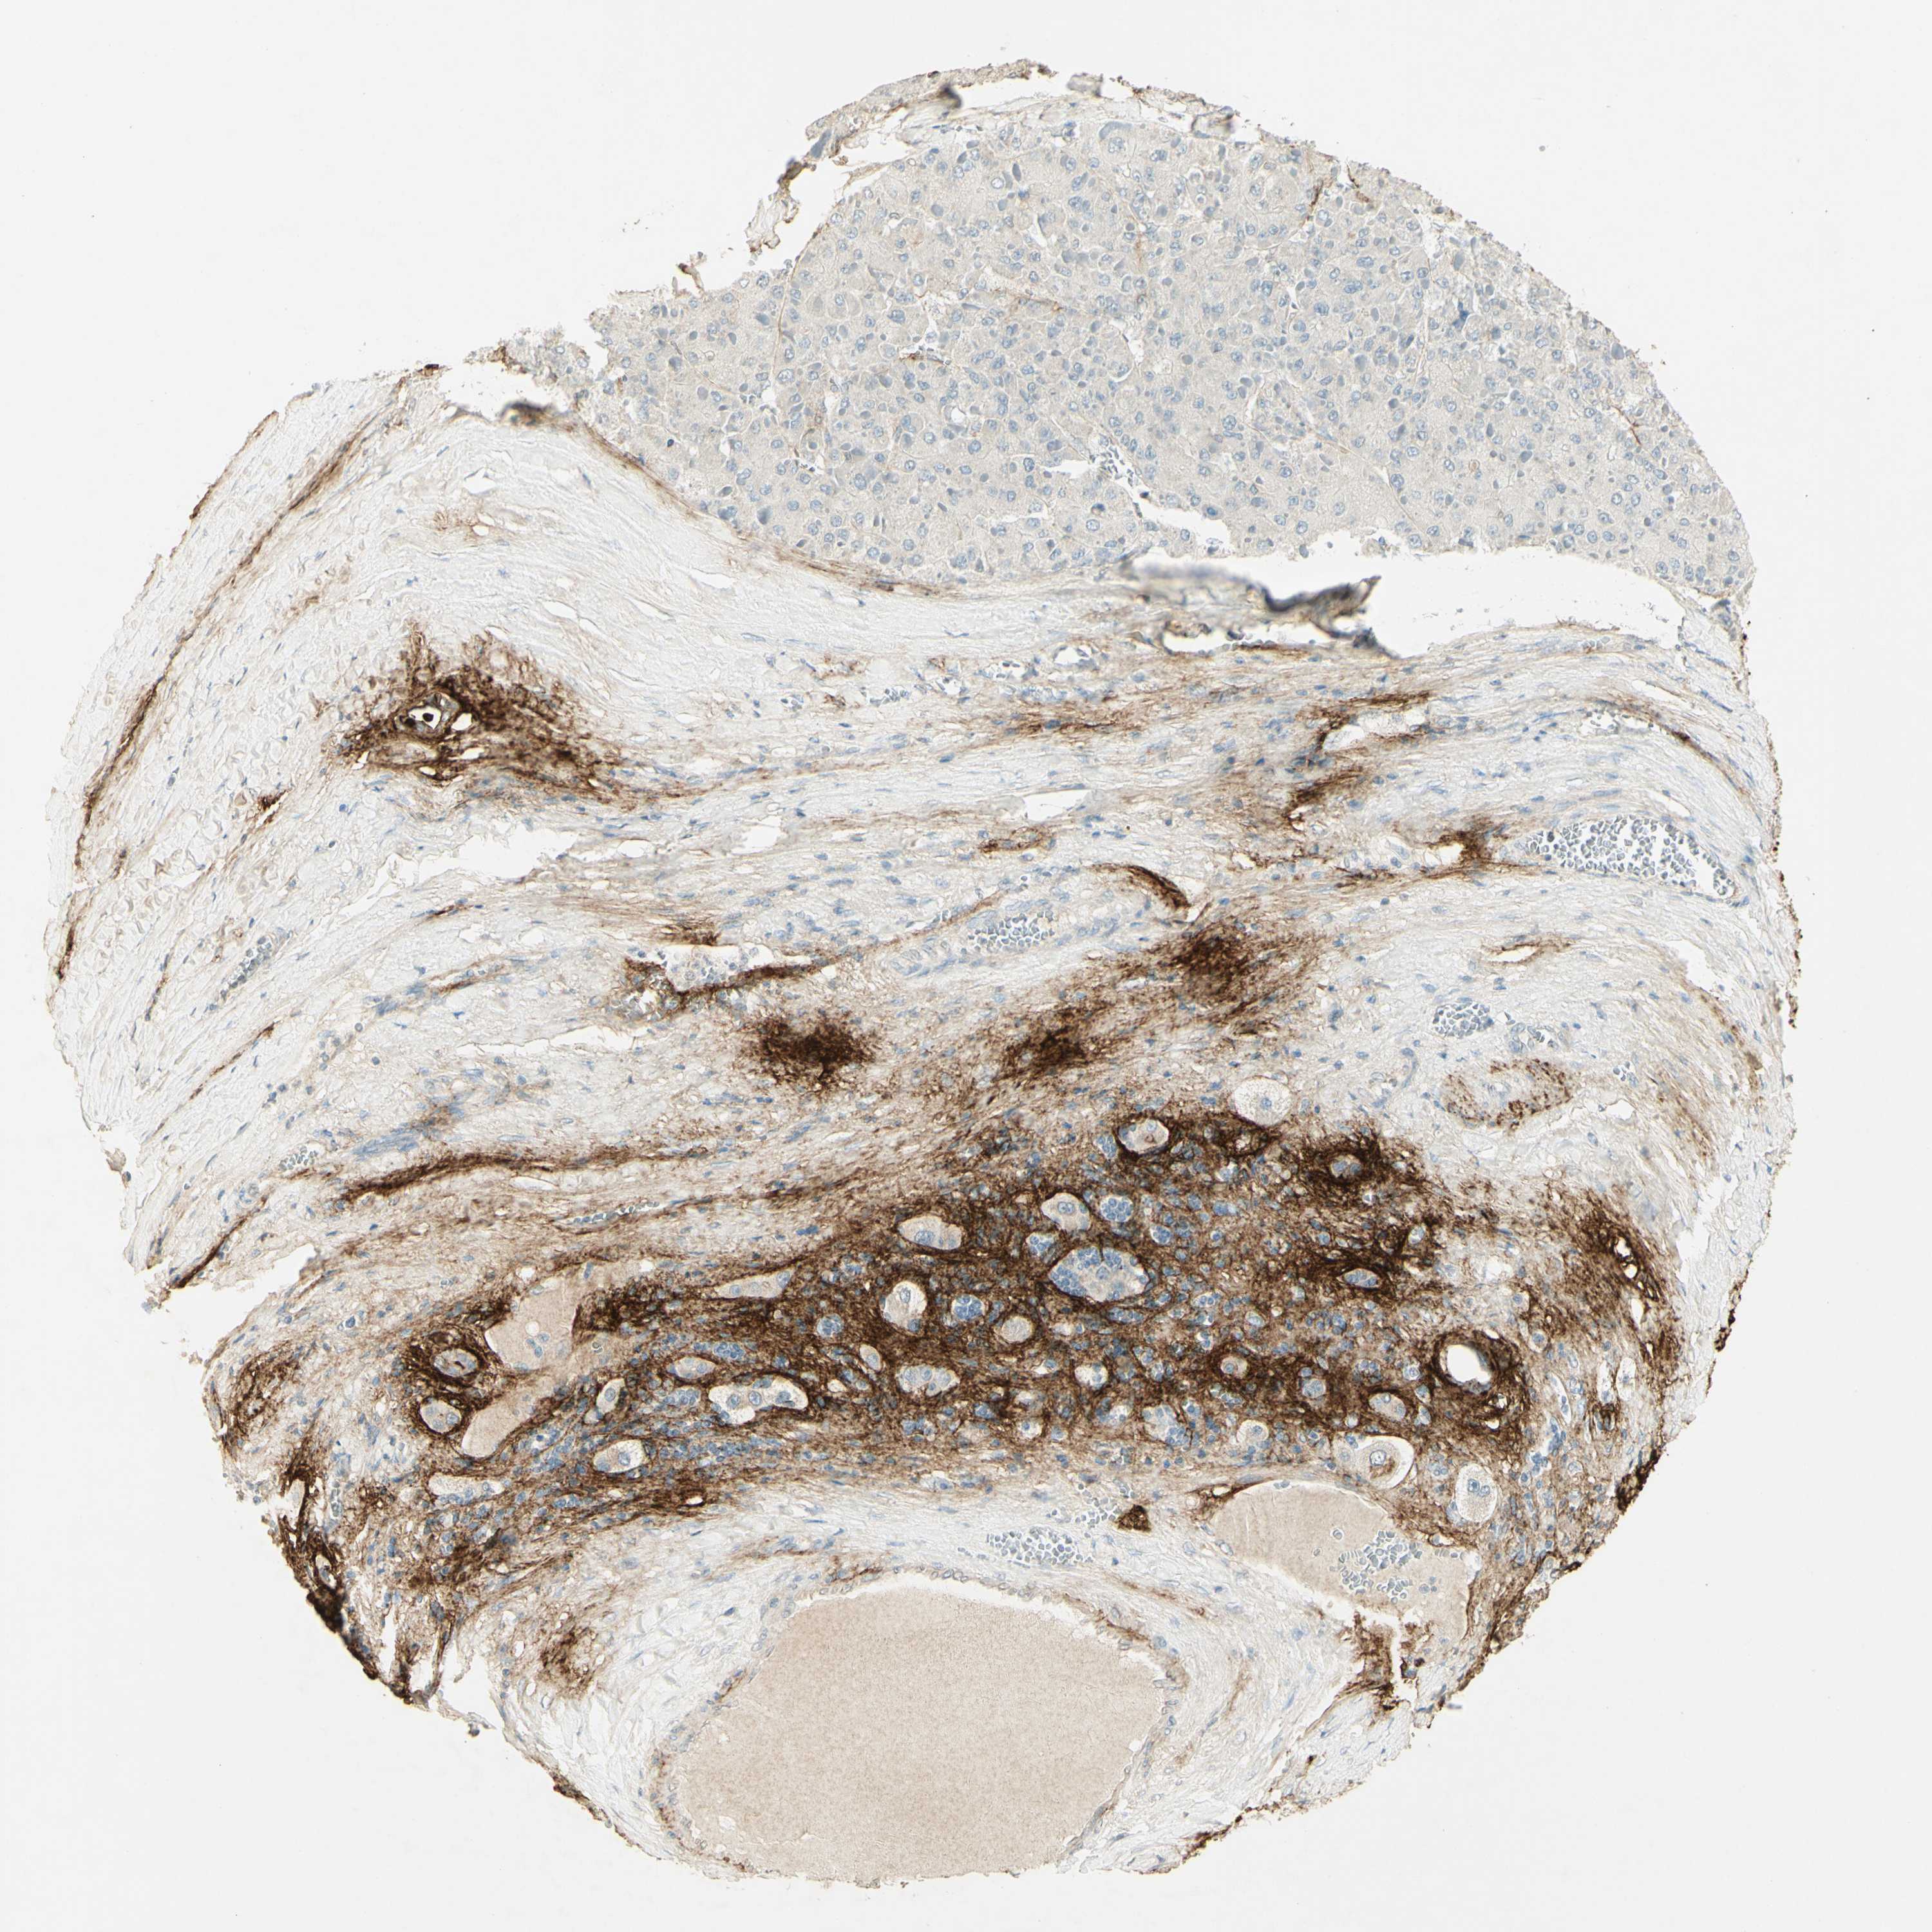

LIVER CANCER - Protein expressioni

A mouse-over function shows sample information and annotation data. Click on an image to view it in a full screen mode. Samples can be filtered based on level of antibody staining by selecting one or several of the following categories: high, medium, low and not detected. The assay and annotation is described here.

Note that samples used for immunohistochemistry by the Human Protein Atlas do not correspond to samples in the TCGA dataset.

Antibody stainingi

Antibody staining in the annotated cell types in the current human tissue is reported as not detected, low, medium, or high, based on conventional immunohistochemistry profiling in selected tissues. This score is based on the combination of the staining intensity and fraction of stained cells.

Each image is clickable and will lead to virtual microscopy that enables deeper exploration of all samples and also displays staining intensity scores, fraction scores and subcellular localization as well as patient and tissue information for each sample.

Antibody HPA026726

Antibody HPA026764

Antibody CAB010907

Staining

High

Medium

Low

Not detected

Intensity

Strong

Moderate

Weak

Negative

Quantity

>75%

75%-25%

<25%

None

Location

Nuclear

Cytoplasmic/membranous

Cytoplasmic/membranous,nuclear

Cholangiocarcinoma

Carcinoma, Hepatocellular, NOS